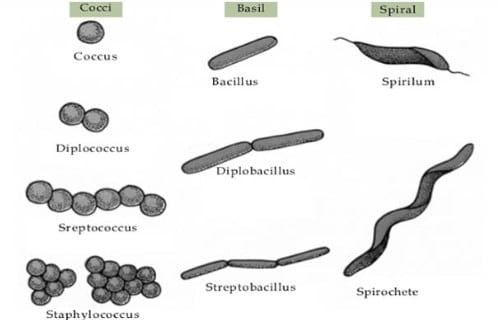

Klasifikasi Bakteri Berdasarkan Bentuk, Pewarnaan Gram, Suhu Dan Kebutuhan Oksigen Lengkap | RuangBiologi.Co.Id

Klasifikasi Bakteri Berdasarkan Bentuk, Pewarnaan Gram, Suhu Dan Kebutuhan Oksigen Lengkap | RuangBiologi.Co.Id

Bentuk Bakteri : Pengertian, Contoh Dan Gambarnya Lengkap | RuangBiologi.Co.Id

Bentuk Bakteri : Pengertian, Contoh Dan Gambarnya Lengkap | RuangBiologi.Co.Id

Biologi Kelas 10 | Apa Saja Dasar Pengelompokan Bakteri?

Biologi Kelas 10 | Apa Saja Dasar Pengelompokan Bakteri?

5 Cara Pengelompokan Bakteri | idschool

5 Cara Pengelompokan Bakteri | idschool